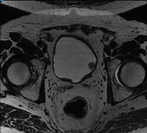

这是我在学校期间参加的一个比赛项目,项目的问题是在医学图像中准确提取膀胱边界以及对肿瘤块的识别。数据集由中国计算机大赛人工智能挑战赛提供。下图是数据集的案例,左图为原始医学图像,右图是人类医学图像专家所做的标注: